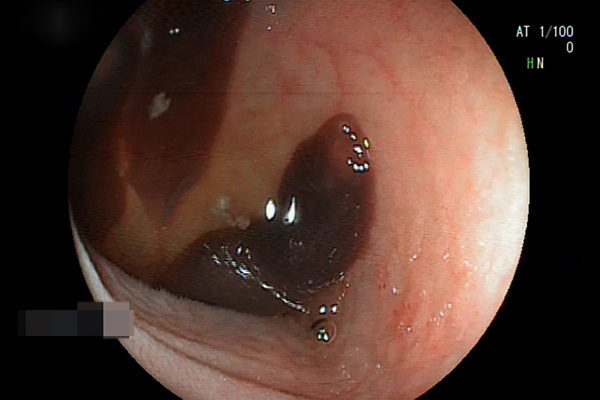

Hàng chục con giòi trong tai của ông L. được gắp ra ngoài

Qua thăm khám, bác sĩ Tiên đã gắp ra được 10 con giòi còn sống trong tai của bệnh nhân L.. Sau khi chụp CT xương chũm và làm các xét nghiệm, bác sĩ Tiên cùng ê-kíp tiến hành phẫu thuật tai bằng phương pháp tiệt căn xương chũm.

Lúc này, các bác sĩ phát hiện phần xương chũm bị ăn mòn toàn bộ tạo thành một hốc rỗng, bộc lộ màng não. Trong hốc mổ, các bác sĩ đã lấy ra thêm 30 con giòi.

“Đây là trường hợp rất hiếm gặp. Việc bệnh nhân không điều trị kịp thời dẫn đến viêm tai xương chũm hoại tử xương, gây biến chứng viêm màng não, áp xe não, tổn thương dây thần kinh số 7, viêm tĩnh mạch bên, sinh giòi trong tai”, bác sĩ Tiên nói.